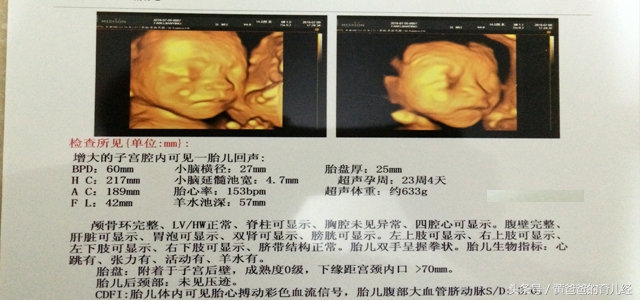

四、第四次彩超是在第23周4天,是四维彩超检查。

这时从图中就可以清晰看出宝宝的头部、手、脚等其他部位了。再次证明胎心率高于140是生女孩是不准确的。最后医生还说一句,很像你,这个难道是暗示我,是男宝宝呢?因为当时不知道,所以心中笑了一下,果然我的是生男孩。